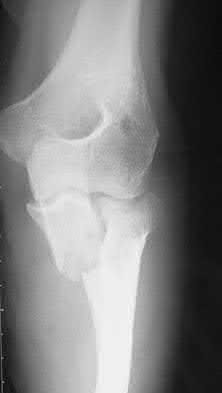

2. # A 35-year-old woman is involved in a head-on collision while driving. Initial radiographs are shown in Figures 8a and 8b. Injury to what vessel increases the risk for osteonecrosis of the injured bone?

The patient has a Hawkins type III talar neck fracture-dislocation with a risk of osteonecrosis ranging from 69% to 100%. Anatomic studies have shown that the artery of the tarsal canal supplies the lateral two thirds of the talar body.

The other vessels listed provide no significant contribution to the talus.